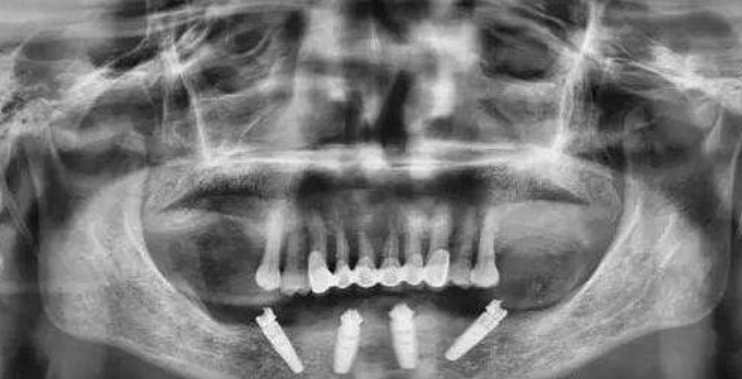

圣洁口腔All-on-4种植技术,针对全口无牙或者半口无牙的情况,仅需要利用4颗种植体,就可以完成半口无牙修复,也就是说全口无牙仅需要8颗种植体,通过把两颗种植体垂直植入牙槽骨内,剩下两颗种植体在中远部位斜角度植入牙槽骨内,然后在种植体的基台上安装“拱形连桥”牙冠即可,不过对医生设计的种植方案有极高要求,每个人的口腔环境不同,牙槽骨内有丰富的神经和血管,对于种植体植入的位置判断,非常重要。

为此圣洁口腔利用独特的数字化种植技术,由圣洁资深种植专家借助高精度的口腔CT设备进行术前检测,得出精准的数据,然后通过数字化技术设计种植方案,对缺牙位置进行精准定位,以及设计3D导板进行设计,让种植牙种植更精准,创伤口更小,术后恢复更快。